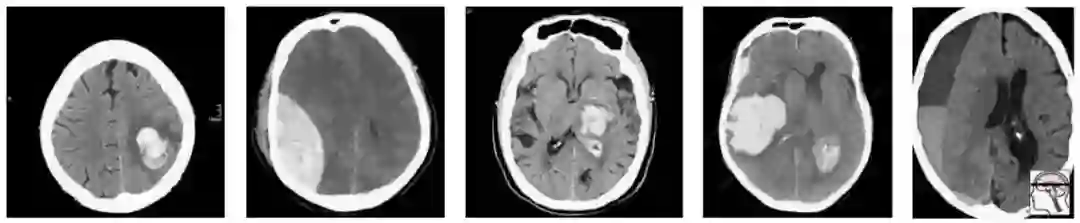

最近,一个新的大型CT脑扫描数据集被发布,其目的是训练模型以检测颅内出血。

在这一人群中,我们有相当合理的“临床”病例组合。3例脑内出血(可能与高血压或中风有关),2例创伤性出血。

现在让我们对这个群体进行抽样,以构建我们的测试集:

随机地,我们抽样得到的大部分是轴外出血。在这项测试中表现良好的模型不一定能在真实的患者身上发挥同样的效果。事实上,你可能期望一个擅长轴外出血而牺牲脑内出血的模型获胜。